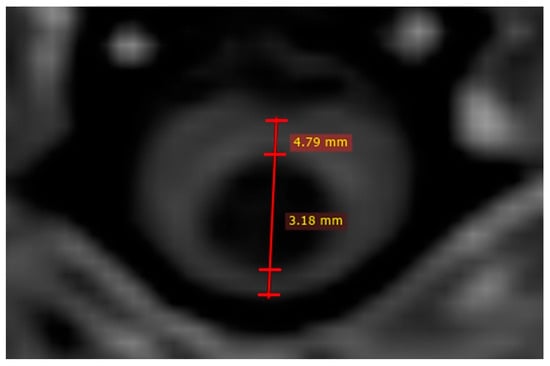

Quantitative measurements were performed for 48 dogs at MRI1 and MRI2. Figure 1 provides an example of the measurement technique. T1W images were used to assess the MSD and MSD/SCD-r in 45/48 dogs, while T2W images were used in the remaining 3/48 dogs. The mean MSD ± SD at MRI1 was 0.99 mm ± 1.52 (median: 0; range: 0.00–5.06) and at MRI2 was 1.35 mm ± 1.57 (median: 0.90; range: 0.00–5.53). The mean difference between the MSD ± SD at MRI1 and MRI2 for the overall population (regardless of treatment) was 0.36 mm ± 0.83 (median: 0.00; range: −1.11–2.40), which was statistically significant (p = 0.0058; CI = 0.180–1.140) (Table 3). The mean MSD/SCD-r ± SD for the overall population (regardless of treatment) was 16.34% ± 23.17% at MRI1 (median: 0%; range: 0–70.01%) and 22.70% ± 24.70% at MRI2 (median: 18.46%; range: 0–74.99%). The mean ± SD within-individual difference in MSD/SCD-r between MRI1 and MRI2 was 6.36% ± 13.67% (median: 0%; range: −15.35–45.05%), which was statistically significant (p = 0.0038; CI= 4.76–19.49%) (Table 3). When considering only the 33 dogs that did not receive furosemide treatment, a similarly significant difference in both MSD and MSD/SCD-r was observed (Table 4). Seven dogs had SM at MRI1 and did not receive furosemide treatment. In this subgroup, neither the mean MSD (p = 0.083; CI: −0.12–1.48) nor the mean MSD/SCD-r (p = 0.270; CI: −7.14–21.24%) differed significantly between MRI1 and MRI2. However, they did show a non-significant trend towards an increase in syrinx size.

Figure 1. Quantitative syrinx measurements on T1W image. Two measurements are performed; one to assess syrinx size (in this case 3.18 mm) and other to assess spinal cord diameter (in this case 4.79 mm).